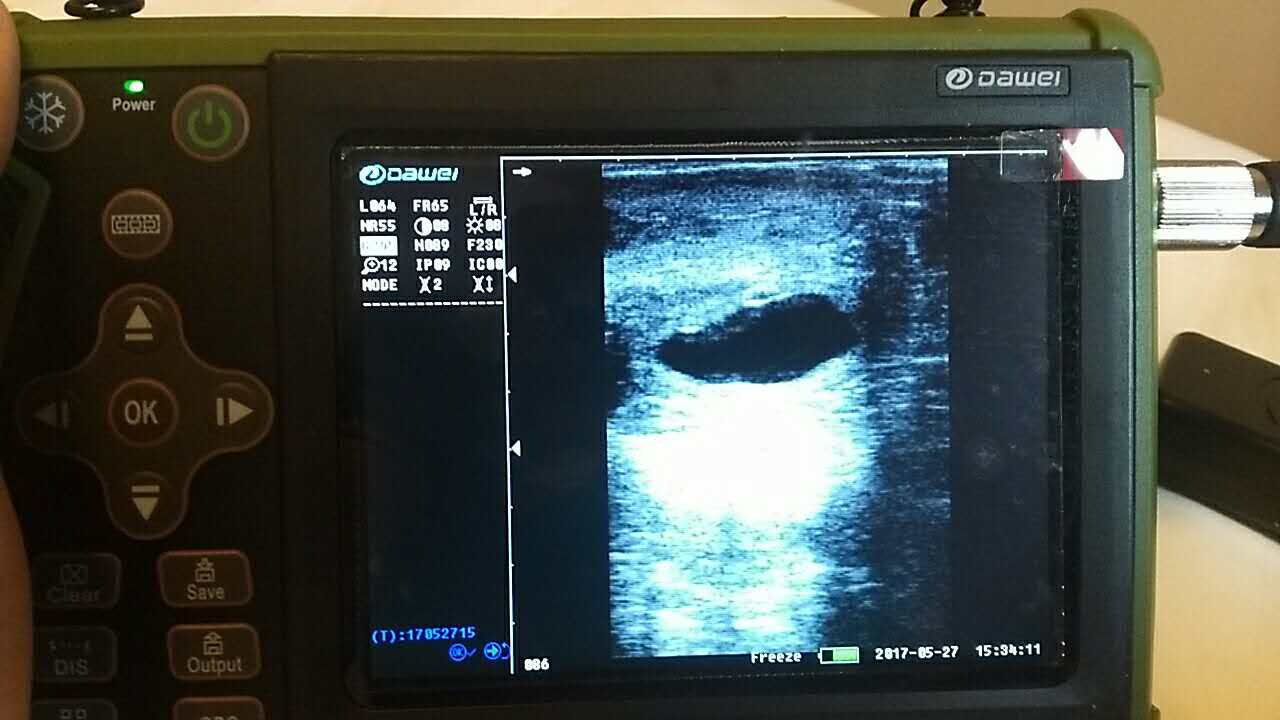

| 羊場(chǎng)母羊照B超辨受孕促增產(chǎn) |

養(yǎng)殖基地140只生產(chǎn)母羊集體接受了B超檢查,利用現(xiàn)代化技術(shù)方法,解決生產(chǎn)母羊繁育難題促進(jìn)畜牧業(yè)生產(chǎn)結(jié)構(gòu)的調(diào)整。 在檢查中,技術(shù)人員拿著B超儀器,給生產(chǎn)母羊做免費(fèi)受孕普查。用B超檢測(cè)母羊受孕情況,用這種方法給母羊做檢測(cè)可以準(zhǔn)確掌握母羊是否受孕、母羊生產(chǎn)周期。通過B超早期孕檢和生殖系統(tǒng)疾病診斷,可以清晰的觀測(cè)到生產(chǎn)的宮腔和胎兒的生產(chǎn)發(fā)育情況。除了幫助基地對(duì)問題羊做出正確診斷,提出合理的治療方案,淘汰無治療價(jià)值的長(zhǎng)期空懷羊,還能提高受孕率,降低飼養(yǎng)成本,有效規(guī)避了假妊娠造成的經(jīng)濟(jì)損失。

檢測(cè)懷孕 估測(cè)胎仔數(shù) 疾病診斷 胎兒活力鑒定 胎心搏動(dòng) 適用對(duì)象:適用于羊、豬、狗等動(dòng)物受孕診斷(集成6種常見動(dòng)物孕周測(cè)量數(shù)據(jù)包) 適用范圍:規(guī)模化豬場(chǎng),人工授精站,飼料/獸藥經(jīng)銷商及企業(yè),科研教學(xué)單位 |